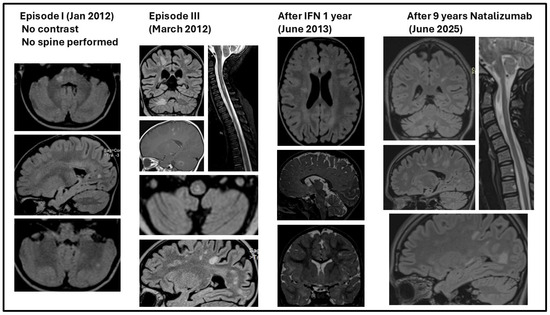

Background/Objectives: Very early pediatric-onset multiple sclerosis (POMS) is rare; clinical studies using disease-modifying treatments (DMTs) have not been performed. Clinicians rely on studies performed at older ages. This review resulted from difficulties faced by clinicians and the off-label use of DMTs at this age. Methods: A literature review of studies dated between 1982 and 2025 on very early POMS, specifically with onset before age 5, has been performed, searching for outcomes without or with DMTs. The curated database of the selected patients was analyzed using computed descriptive and integrated cohort-level estimates. The clinical, paraclinical, treatment, and outcome characteristics were analyzed. Statistical analysis used JASP, with GenAI-assisted verification. The treatment outcome of a 16-year-old patient with very early POMS starting at 2 years 4 months that consecutively received interferon, immunoglobulin, and Natalizumab is presented. Results: A total of 101 patients with very early POMS presented, at onset, with ataxic syndrome (57.4%), pyramidal syndrome (41.4%), ophthalmoplegia (10.3%), and optic neuritis (6.9%). In evolution, 22.7% had seizures. Half of the patients were not treated. Among those treated, acute steroid therapy was administered; 11 received the DMTs interferon, Glatiramer acetate, Dimethyl fumarate, and Azathioprine (three), with only two high-efficacy therapies (Natalizumab and Rituximab). Our patient had partial remission under interferon, relapses when stopped and replaced by immunoglobulin and 9 years relapse-free interval when Natalizumab was introduced. Conclusions: Early treatment with high-efficiency DMTs should be considered in very early POMS; association with known increased neuroplasticity at this age may improve prognosis, allowing good recovery of acquired disability. Full article

Figure 1